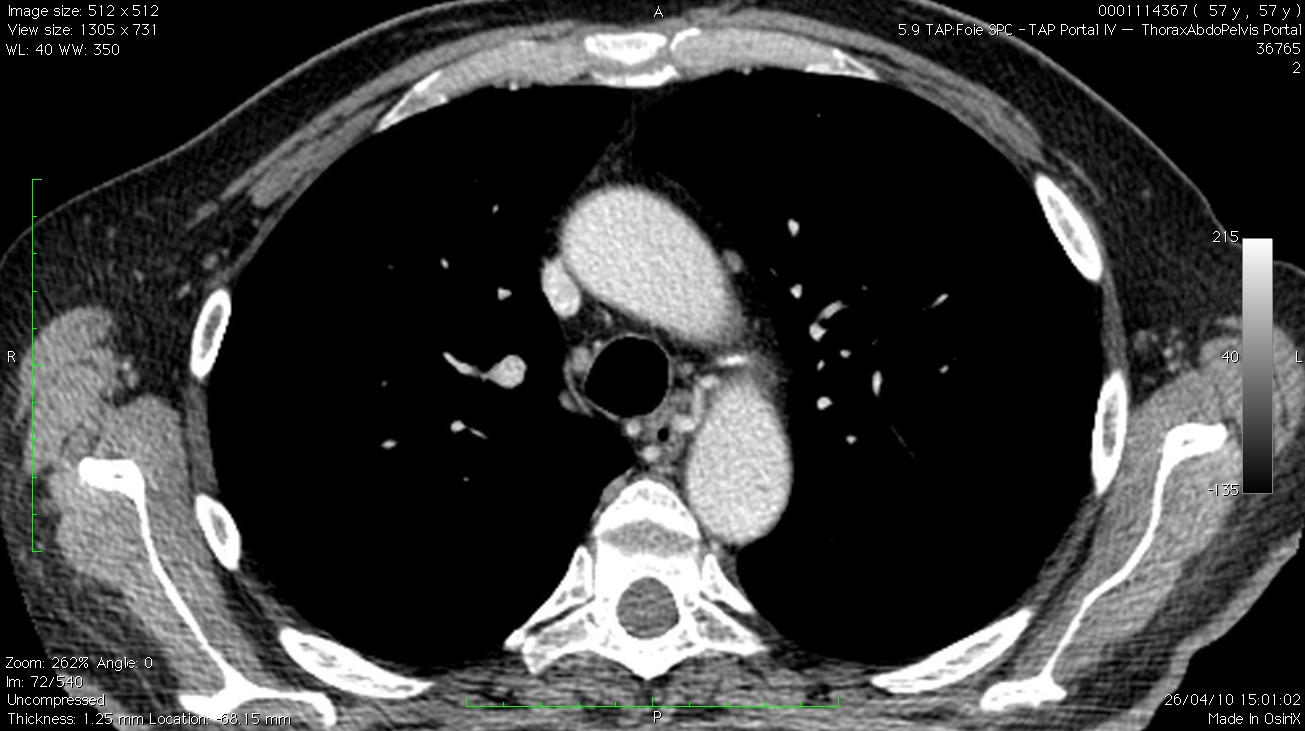

L’ETO retrouve sur la face postérieure de l’aorte un petit flux émergant d’un ostium de 3 mm.

Le flux est en fait un flux d’artériole à basse vitesse et avec une composante diastolique, et non un flux continu de shunt arterio-veineux comme le suggérait l’ETT. Il ne s’agit donc clairement pas d’un canal artériel persistant, les vélocités sont trop faibles, la localisation n’est pas la bonne, et le flux ressemble à une branche périphérique de l’aorte.

En regardant le scanner avec le radiologue, il s’agit en fait une artère bronchique ectasique naissant de la face postérieure de la crosse. Cette dilatation est elle en rapport avec l’EP massive survenue quelques mois plus tôt??? (La collatéralité par des artères bronchiques sur des EP importantes a déjà été décrite)